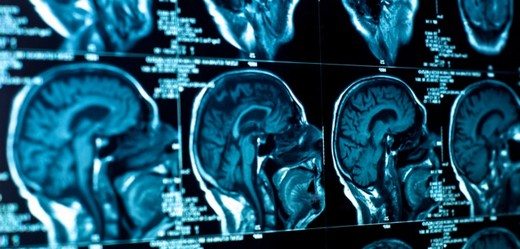

Daha öncesinde stresli olaylar yaşasa bile kişisel veya ırsi olarak herhangi bir akıl hastalığı olmadığı tespit edildi. Nörolojik bulgular da normal olmasına karşın, bilgisayarlı tomografi ve manyetik rezonans görüntüleme esnasında beyinde dev bir tümör olduğu belirlendi. Beynin sol ön lobunda keşfedilen meningiomatosis tümörü yaygın görülen iyi huylu bir tümör. Tümörün görüldüğü bölgenin depresyonda önemli bir rolü olduğu biliniyordu. Sonrasında hasta acil ameliyata alınarak, tedavi sağlandı. Depresyona ilişkin sendromların 1 ay içinde yok olduğu görüldü.

Depresyon,delilik, halüsinasyon, anksiyete bozuklukları ve anoreksiya nervosa gibi psikiyatrik semptomların nörolojik sinyaller vermese de beyin tümörlerinin nedeni olabileceğine değinildi. Her ne kadar depresyon hastalarında beyin taraması yapmak, pek gerçekçi değil. Çünkü depresyonda beyin tümörleriyle karşılaşmak oldukça nadir. Doktorlar 50 yıl sonrasında gerçekleşen depresyon sendromlarında, eğer depresyon tedavisine direnç varsa ya da tedaviye duyarsız kalıyorsa bilgisayarlı tomografi ve manyetik rezonans görüntüleme tavsiye ediliyor.